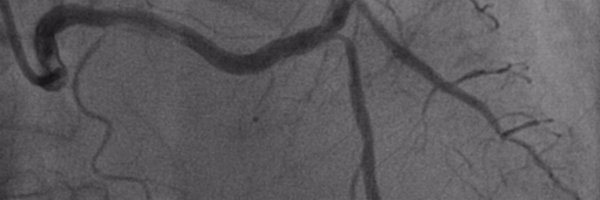

70's, DM, ESRD, CVA, frail, prior PCI to prox LAD and OM1, presents with NSTEMI. Angio shows L dominant, short LM with severe disease (abnormal dFR in LAD and LCx). Referred for CABG, turned down at 2 different centers. 2 admissions in a month for syncope/CHF. Referred for PCI